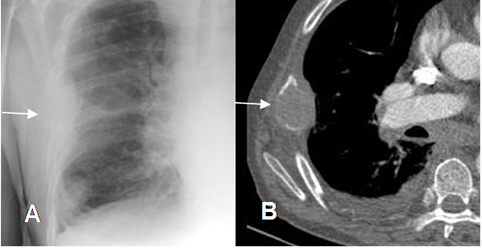

Fig 39. Lesión extrapelural.

A: Rx PA y B: TAC axial. Imagen densa con ángulos obtusos, que ocasiona destrucción del arco costal, lo que confirman su localización extrapleural.